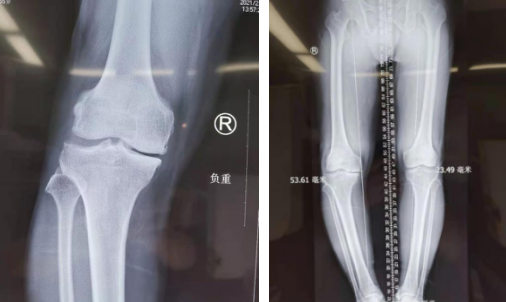

听从儿女建议,万大姐来到必威官方首页官网betway关节科就诊,门诊医生询问病史、查体,万大姐右下肢内翻畸形,右膝关节肿胀,右下肢比左下肢短约2厘米;结合影像检查,诊断为:右膝关节骨性关节炎,右膝关节半月板损伤,右膝关节游离体。

术前

张传开主任团队评估万大姐的膝关节炎为中度,万大姐年纪还不大,应首选保膝治疗。这是一种既能纠正畸形减轻疼痛,又可保留患者自然的膝关节,最大程度地保留关节的运动功能和舒适性的一种治疗方案。团队讨论后,决定采用关节镜探查、机器人精准定位截骨,微创完成这起保膝手术。